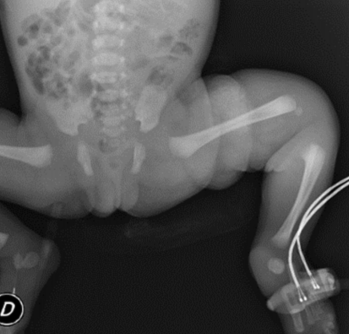

A las 56 h de vida se constata zona indurada con eritema y rubor en región de muslo izquierdo de 12 por 8 cm aproximadamente (Figura 1), con dolor a la palpación y extensión del miembro, en apirexia. No se evidencia puerta de entrada ni zona de punción. Se destaca tinte ictérico hasta abdomen, resto sin particularidades. Con planteo de celulitis de muslo izquierdo reingresa a unidad neonatal. Se realiza paraclínica infecciosa (Tabla 1), radiografía de cadera y miembro inferior izquierdo (Figura 2). Se inicia vancomicina i/v y analgesia. En la evolución agrega llanto, irritabilidad inconsolable y vómitos, deposiciones normales, en apirexia. Del examen físico se destaca fontanela anterior normotensa, abdomen blando, depresible, sin defensa, moviliza los cuatro miembros. Se traslada a centro de tratamiento intensivo (CTI) para continuar valoración. Permanece en CTI 26 días. Se realizó punción lumbar aproximadamente 12 h después de haber comenzado antibióticos, sin aislarse germen (Tabla 2). Hemocultivo a las 56 h de vida en la maternidad del Hospital Las Piedras y hemocultivo al ingreso a CTI, ambos desarrollaron Streptococcus agalactiae sensible a penicilina. A las 12 h de ingresada en CTI se realizó drenaje quirúrgico de articulación de rodilla izquierda que confirma osteoartritis supurada, buena evolución, se aisló Streptococcus agalactiae (Tabla 3). Con planteo de sepsis connatal precoz a Streptococcus agalactiae, con meningitis aguda supurada y osteoartritis de rodilla izquierda, recibe tratamiento de primera línea con ampicilina y gentamicina por 21 días. Requirió intubación orotraqueal (IOT) por 24 h, cargas de volumen e inotrópicos por 48 h. Presentó alteración inicial de la crasis y anemia normocítica normocrómica, por lo que se realizó reposición con plasma y glóbulos rojos. Hidratación parenteral por 72 h, luego aporte vía oral, dada la intolerancia digestiva alta recibió tratamiento con omeprazol y ondansetrón. Examen neurológico normal.

Figura 2: Recién nacido. Sepsis precoz a S. agalactiae. Radiografía de cadera y miembros inferiores, a las 56 h de vida

Estudios imagenológicos: ecografía transfontanelar, torácica y abdominal a los 3 días de vida normales, se destaca derrame pleural simple bilateral a predominio izquierdo, resto normal. Se reitera ecografía transfontanelar a los 10 días de vida sin alteraciones. Ecocardiograma Doppler a los 10 días de vida normal. Tomografía de cráneo a los 15 días de vida normal. Radiografía de rodilla a los 20 días de vida: a nivel de fémur distal calcificación de partes blandas de mayor entidad en cara posterior, sin clara evidencia de deformación del periostio, núcleo de osificación femoral desplazado hacia atrás, aumento de la densidad del sector proximal de tibia como se observa en el edema de procesos infecciosos. Resonancia nuclear magnética de cráneo a los 22 días de vida sin alteraciones.

La osteoartritis séptica es un cuadro grave, relativamente frecuente en pediatría. La rodilla y la cadera son las articulaciones más afectadas, siendo elevado el riesgo de complicaciones. La detección de la infección puede ser difícil, sobre todo en neonatos. En este paciente se planteó inicialmente una celulitis de miembro inferior, realizándose posteriormente diagnóstico de osteoartritis de rodilla izquierda, realizando punción articular y logrando identificar el germen. Según diversos estudios, la osteoartritis séptica es mayormente monoarticular, como ocurrió en este caso. Como factores de riesgo para desarrollar osteoartritis se han identificado la colocación de vías venosas centrales y periféricas, cateterizaciones umbilicales y venopunciones múltiples; no existiendo dichos desencadenantes en este paciente. La evolución sin secuelas depende del diagnóstico y tratamiento precoz, es de gran importancia el alto índice de sospecha clínica y el abordaje quirúrgico temprano, como también el tratamiento ortopédico adecuado12-14.